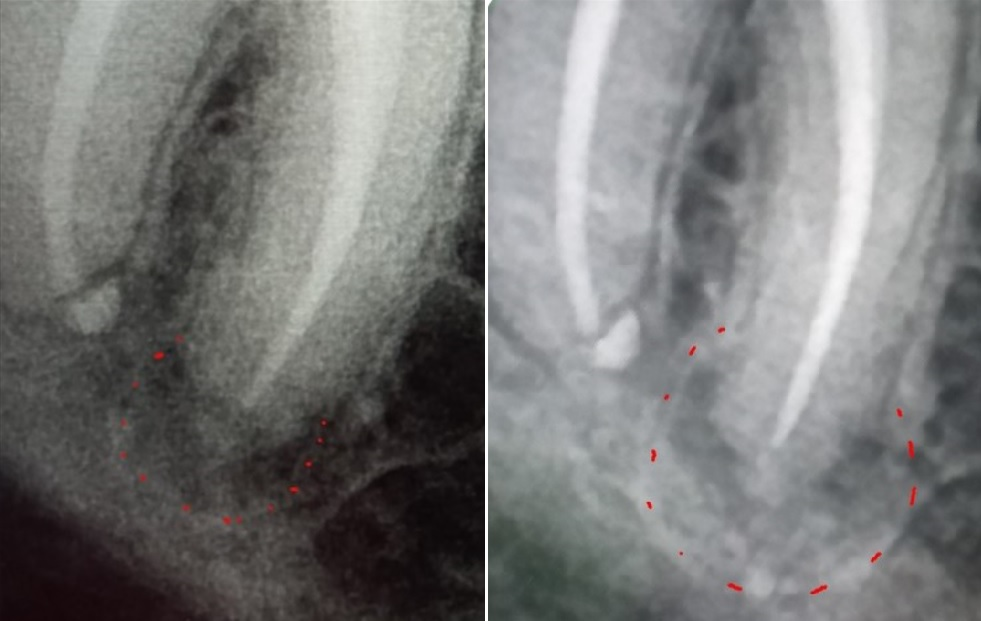

alewka213213 Опубликовано 10 декабря, 2024 Автор Поделиться Опубликовано 10 декабря, 2024 (изменено) В 08.12.2024 в 19:48, Carioznik сказал: Дело в инфекции, которая находится внутри зуба, а за пределами зуба -это её следствие. Нет зуба - нет инфекции. Это вариант удаления, он даёт 100% результат. Почистить каналы -тоже равно убрать инфекцию. Это вариант лечения, но даёт уже не 100 % результат. Хочется сохранить зуб (показаний к удалению, кстати, пока не видно) - перелечивайте. Не хотите лечить - удаляйте. Решать Вам. Cходил, чтобы перелечить, но решили не делать этого, так как врач заметил, что кажется воспаление уменьшается! И это при том что зуб без нерва, мы ничего не делали, а оно вон как... Или нам кажется? По крайне мере увеличения вроде нет. Вот, тоже выскажите мнение, пожалуйста. Пол года назад: Сейчас: Изменено 10 декабря, 2024 пользователем alewka213213 Ссылка на комментарий

Carioznik Опубликовано 10 декабря, 2024 Поделиться Опубликовано 10 декабря, 2024 (изменено) 57 минут назад, alewka213213 сказал: кажется воспаление уменьшается! Оченивать динамику нужно по КТ. По обычным снимкам всё может быть очень обманчиво. В зависимости от проекции (а её невозможно, при обычном снимке, сделать одинаковую)- будет разный размер. Вот вам пример: посмотрите на свою ладонь, а потом поверните ее ребром (сначала она была по площади - большая, а когда повернули - стала вдруг уже маленькая) Изменено 10 декабря, 2024 пользователем Carioznik 1 Ссылка на комментарий